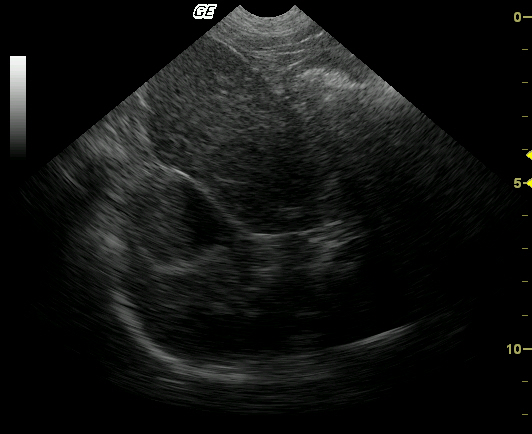

This 14-year-old MN Springer Spaniel was presented for decreased appetite, vomiting, and melena that was non responsive to medical therapy. The clinical condition was rapidly declining. The physical exam was uneventful. Blood analysis revealed a progressively, mildly elevated ALT and mildly elevated SAP in serial samples over a 3-week period